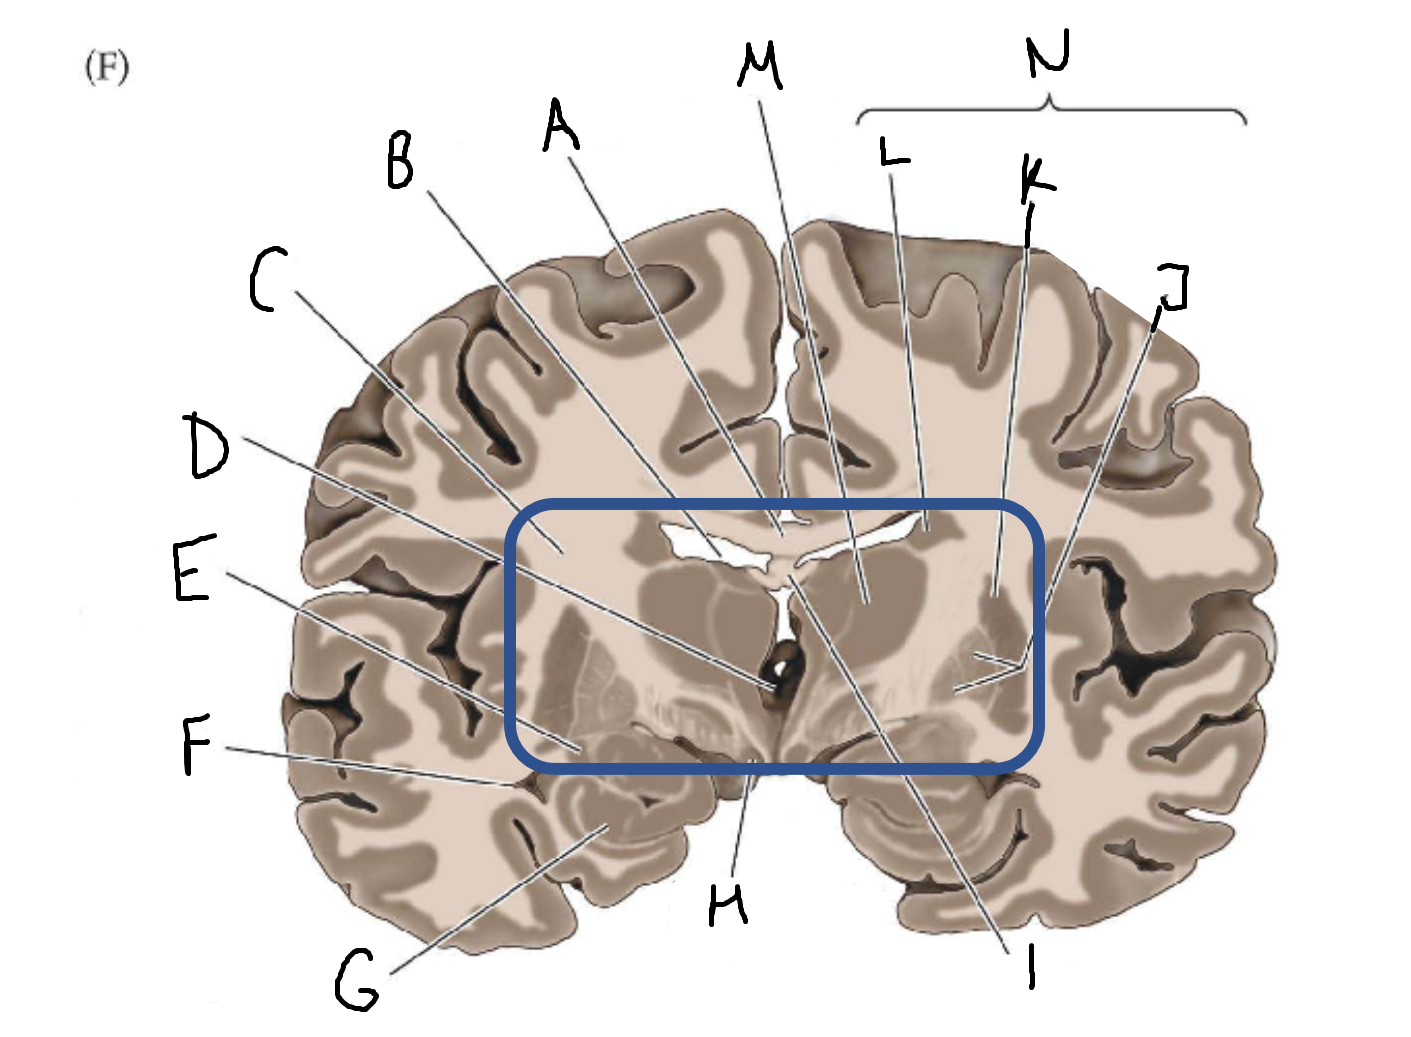

A

corpus callosum

B

lateral ventricle

C

internal capsule

D

third ventricle

E

tail of caudate nucleus

F

lateral ventricle

G

hippocampus

H

mammillary body

I

fornix

J

globus pallidus

K

putamen

L

caudate

M

thalamus

N

basal ganglia